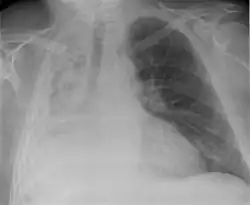

| Other names | Collapsed lung[1] |

| Atelectasis of a person's right lung | |

Atelectasis is the partial collapse or closure of a lung resulting in reduced or absence in gas exchange. It is usually unilateral, affecting part or all of one lung.[2] It is a condition where the alveoli are deflated down to little or no volume, as distinct from pulmonary consolidation, in which they are filled with liquid. It is often referred to informally as a collapsed lung, although more accurately it usually involves only a partial collapse, and that ambiguous term is also informally used for a fully collapsed lung caused by a pneumothorax.[1]

Clinically significant atelectasis is generally visible on chest X-ray; findings can include lung opacification and/or loss of lung volume. Post-surgical atelectasis will be bibasal in pattern. Chest CT or bronchoscopy may be necessary if the cause of atelectasis is not clinically apparent. Direct signs of atelectasis include displacement of interlobar fissures and mobile structures within the thorax, overinflation of the unaffected ipsilateral lobe or contralateral lung, and opacification of the collapsed lobe. In addition to clinically significant findings on chest X-rays, patients may present with indirect signs and symptoms such as elevation of the diaphragm, shifting of the trachea, heart and mediastinum; displacement of the hilus and shifting granulomas.[13]